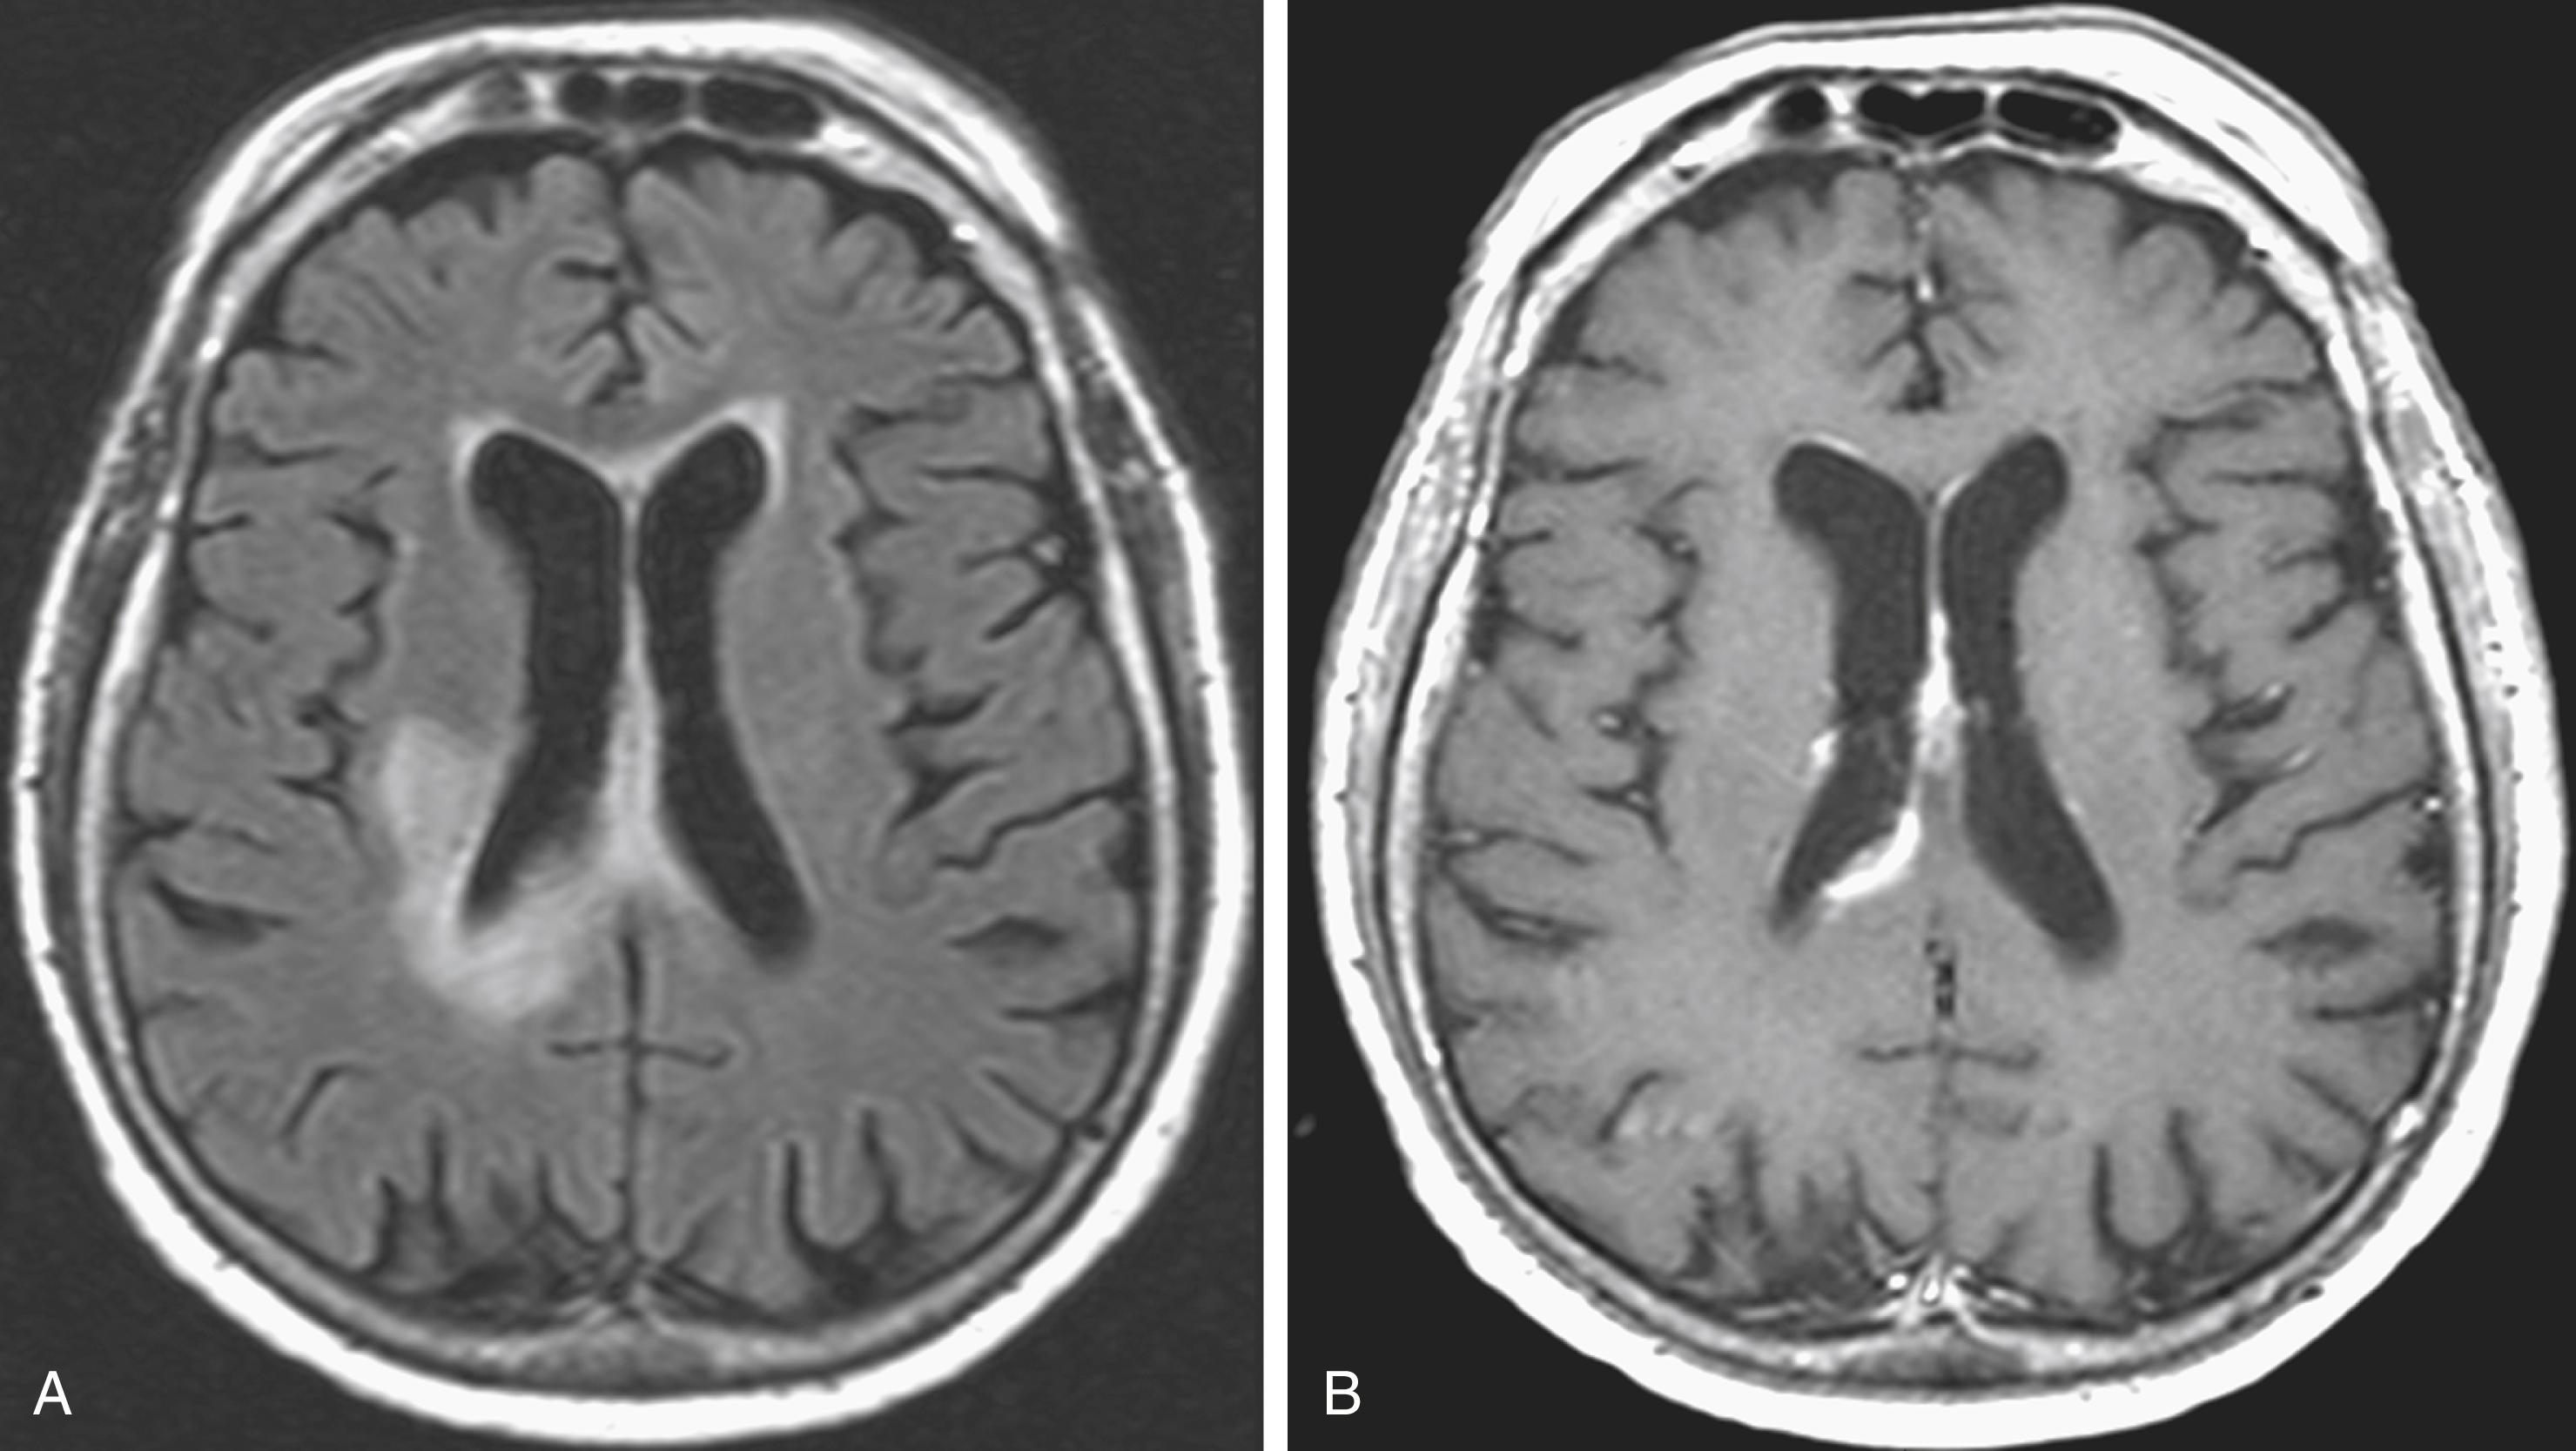

Gliomatosis cerebri was previously considered a distinct entity, but since the 2016 update to the WHO classification of CNS tumors , it is now being considered a growth pattern of many gliomas, most commonly, anaplastic astrocytoma. The glial tumor cells are disseminated throughout the parenchyma and infiltrate large portions of the neuraxis. Macroscopically it appears homogeneous and is seen as enlargement/expansion of the parenchyma; the gray/white matter interface may become blurred, but the architecture is otherwise not altered. Unilateral hemispheric white matter is generally involved first; then the pathology spreads to the contralateral hemisphere through the corpus callosum. Later, the deep gray matter (basal ganglia, thalamus, massa intermedia) may be affected as well. Diffuse tumor infiltration often extends into the brainstem, cerebellum, and even the spinal cord. Histologically, most cases of gliomatosis cerebri are WHO grade III.

The MRI appearance is iso- to hypointense on T1 and hyperintense on T2. Hemorrhage is uncommon, and enhancement is also rare, at least in the early stages ( Fig. 40.19 ). Later, multiple foci of enhancement may appear, signaling more malignant transformation. The imaging appearance is similar to that of autoimmune or infectious encephalitis, including subacute sclerosing panencephalitis, but in these disorders, clinical findings are more pronounced.

Fig. 40.19, Gliomatosis Cerebri.